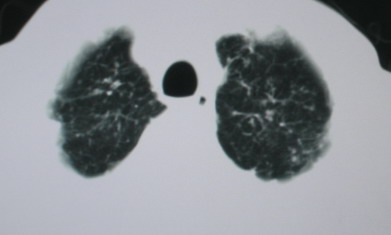

以下是引用卜一在2008-6-3 19:33:00的发言:[br]双肺结节,以双上肺分布为多,期间搀杂片状致密影及索条致密影。考虑:继发性肺结核伴血型播散可能性大。不除外肺泡ca的可能!另:椎体退变!

以下是引用医影拾贝在2008-6-3 18:48:00的发言:[br]双上肺弥漫性小结节影,纵隔窗内钙化淋巴结影,考虑血播性tb可能性较大,不除外肺ca可能

以下是引用panyishengct在2008-6-3 21:09:00的发言:[br]双上肺弥漫性小结节影,纵隔窗内钙化淋巴结影,考虑矽肺或/和tb可能性较大,不除外肺ca可能。腰椎考虑退变。 [br][br]